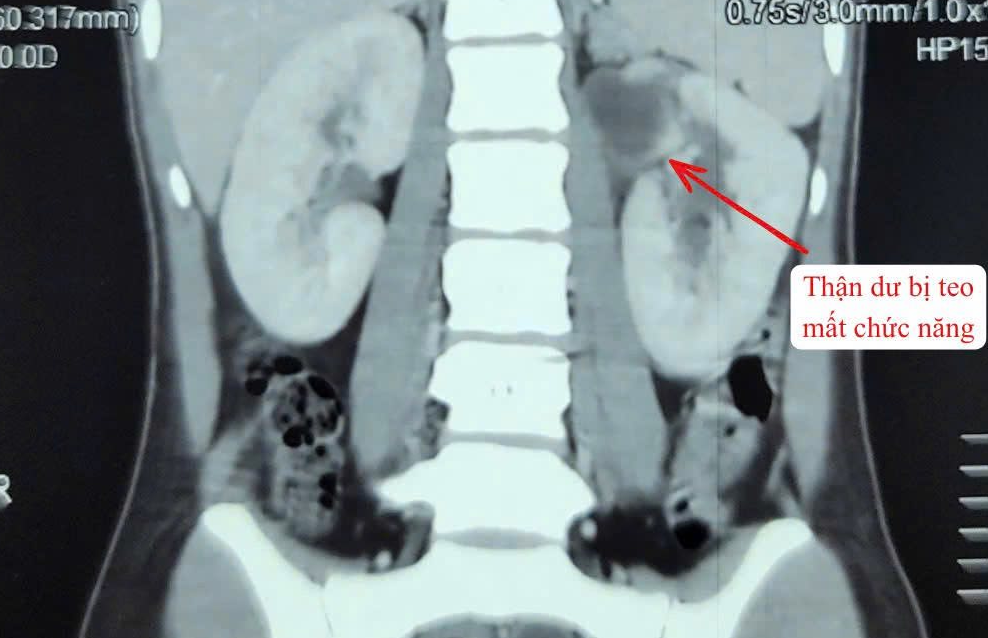

Người bệnh nhập viện trong tình trạng sốt cao, đau vùng hông trái. Qua thăm khám lâm sàng và thực hiện các xét nghiệm cận lâm sàng, các bác sĩ chẩn đoán bệnh nhân mắc dị tật thận - niệu quản đôi bên trái (tổng 3 thận). Trong đó, một thận đã mất chức năng, niệu quản giãn lớn bất thường, chứa nhiều mủ gây nhiễm trùng nặng.

Hình ảnh thận trên phim. Ảnh: BVCC.